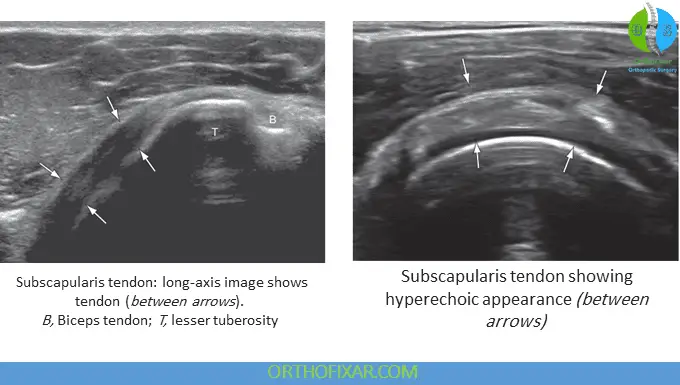

Subscapularis Tendon Ultrasound

Examination of the subscapularis tendon requires positioning the shoulder in lateral rotation. The initial transducer placement should be in long axis orientation, parallel to the tendon fibers. The tendon should demonstrate hyperechoic characteristics and can be traced laterally to its insertion on the lesser tubercle of the humerus.

Comprehensive examination requires viewing the tendon in its entirety from superior to inferior aspects, with particular emphasis placed on the superior insertion site, as this location represents the most commonly injured area in association with supraspinatus rotator cuff tears. Rotating the transducer 90 degrees allows visualization of the subscapularis tendon along its short axis. Just above the outline of the humeral head, a transverse cross-section of the subscapularis becomes visible. It is normal to observe areas of hypoechoic striations representing muscle tissue or interfaces between the several tendon bundles.